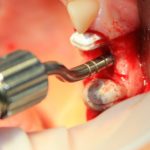

В ходе проведения операции синуслифтинга, у нас образовалась небольшая перфорация шнайдеровой мембраны:

Мы начинаем с того, что выводим ее в центр апертуры, попутно мобилизуем края. В результате, она несколько уменьшилась в размерах: